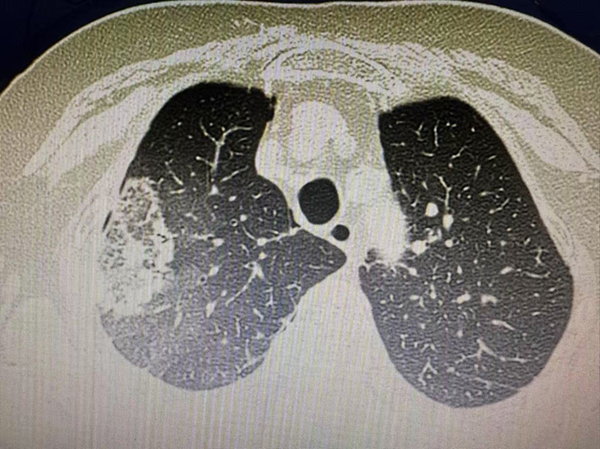

治疗前CT

家住沈阳市铁西区的张奶奶,8月下旬在市五院胸外科门诊做双肺CT常规检查时,发现左肺上叶有一直径2.1厘米的实性结节,该结节形态不规则,边缘呈毛刺状,是典型的肺癌影像学改变。手术是这类病症的首选治疗方案,但张奶奶年事已高,对全麻手术十分抗拒,加之儿女远在国外,家里只有她和老伴两个人,她不仅要照料自己,还要承担起照顾生活无法完全自理的老伴的重任,因此希望能有其他治疗办法。胸外科团队经过多轮病例分析和方案推演,最终为她定制了局麻下微创消融术的治疗方案。